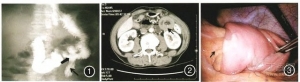

NEJM病例学习:腺瘤致空肠肠套叠

近日由Paul Burgers博士提供的一则肠套叠病例发表在新英格兰杂志上。52岁男性,既往体健,伴发上腹部疼痛、恶心,遂来我院就诊。CT检查结果显示肠套叠。保守治疗效果显著,治愈出院三天后,在等待进一步的诊断结果时 ...